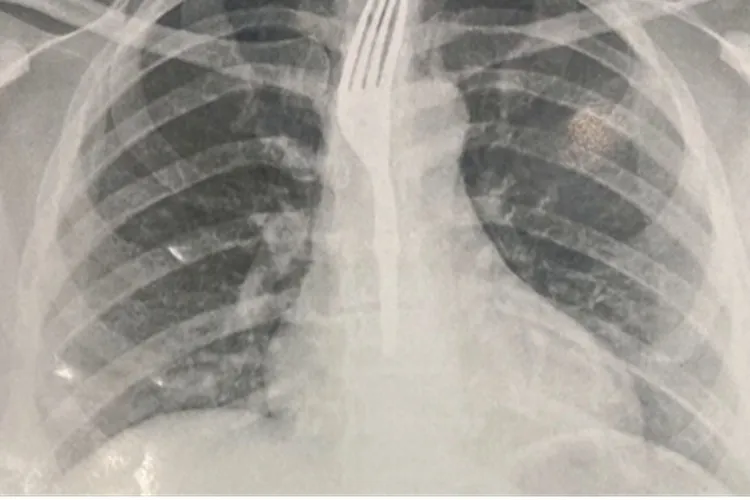

Mulher engole garfo durante refeição em Guanambi Foto Ilustrativa

Uma situação incomum chamou a atenção em Guanambi na última sexta-feira (26). Uma mulher precisou ser socorrida após engolir um garfo enquanto fazia uma refeição. Ela deu entrada no Hospital Geral de Guanambi (HGG), onde exames de imagem apontaram que o objeto estava alojado no esôfago em posição de risco. Diante da gravidade, os médicos decidiram transferir a paciente para Vitória da Conquista, onde deve passar por procedimento especializado para retirada do utensílio.